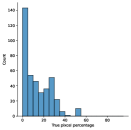

The main purpose of these experiments is to find the effect of using synthetic data generated from the SinGAN-Seg pipeline instead of small real datasets because the SinGAN-Seg pipeline can generate an unlimited number of synthetic samples per real image. A synthetic sample consists of a synthetic image and the corresponding ground truth mask. Therefore, experts’ knowledge is not required to annotate the ground truth mask. For these experiments, we have selected the best parameters of the SinGAN-Seg pipeline from the experiments performed under Section Synthetic data versus real data for segmentation. First, we created small sub-datasets from the real polyp images from fold one such that each dataset contains number of images, where can be one of the values of . The corresponding synthetic dataset was created by generating synthetic images and corresponding masks per real image. Then, our synthetic datasets consist of number of images such that . Then, we have compared true pixel percentages of real masks and synthetic masks generated from the SinGAN-Seg pipeline using histograms of bin size of . The histograms are depicted in Fig 10. The first row represents the histograms of real small detests, and the second row represents the histograms of corresponding synthetic datasets. Compare pairs (one from the top row and the corresponding one from the bottom) to get a clear idea of how the generated synthetic data improved the distribution of masks.

The UNet++ segmentation models were trained using these real and synthetic datasets separately. The synthetic dataset is generated using style transfer ratio because it shows the best performance in the experiment, which uses only fake data to train segmentation models as presented in Table 2 in addition to the best SIFID values presented in Table 1. Then, we have compared the performance differences using validation folds. In these experiments, the training datasets were prepared using fold one. The remaining two folds were used as validation datasets. The collected results from the UNet++ models trained with the real datasets and the synthetic datasets are tabulated in Table 3. A comparison of the corresponding IOU scores are plotted in Fig 11.